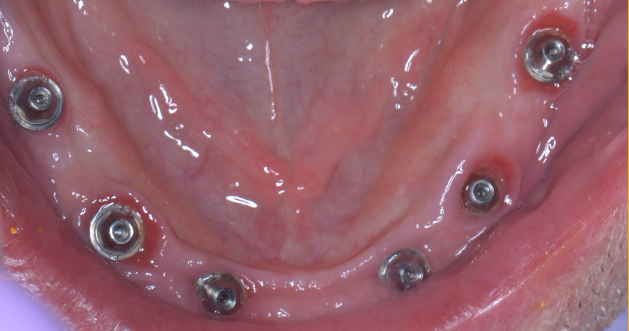

Pe baza scanărilor imagistice 3D (CBCT) se vor efectua măsurători ale înălțimii și lățimii osului mandibular, astfel încât medicul implantolog să poată decide dacă se pot insera implanturi direct sau este nevoie de adăugare de os în prealabil. Se realizează un ghid chirurgical care ajută la poziționarea precisă a implanturilor în os (Fig.3.6.4. dr. Ondine Lucaciu), iar în 24 de ore după această intervenție pacientul primește o punte provizorie fixă pe care o va purta un interval de 3-6 luni, perioadă necesară osteointegrării implanturilor, respectiv vindecării (Fig. 3.6.5). Această lucrare provizorie va fi înșurubată în 6 puncte, în cele 6 implanturi inserate în mandibulă (Fig. 3.6.6).

După acest interval lucrarea provizorie se îndepărtează, în fiecare implant se montează câte un dispozitiv necesar realizării amprentelor (Fig. 3.6.7) care vor servi tehnicianului dentar pentru realizarea punții definitive (Fig. 3.6.8 și Fig. 3.6.9). Realizarea acesteia se face în câteva zile, interval în care pacientul va continua să poarte lucrarea provizorie realizată inițial.